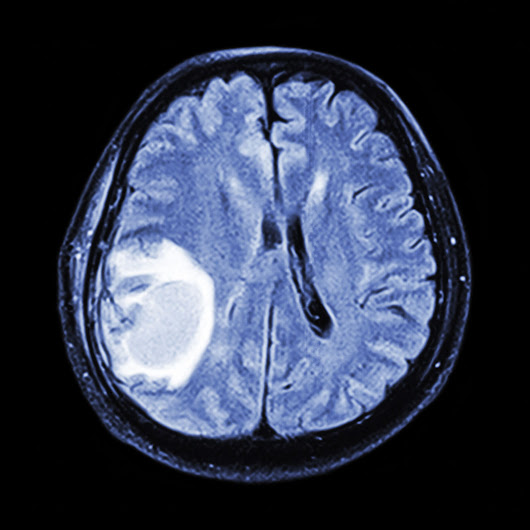

There are numerous distinct images of the brain that may be obtained with or without intravenous contrast using Computed Axial Tomography (CAT scan/CT).

Powerful magnets and radio waves are used in Magnetic Resonance Imaging (MRI) to provide a clear image of the brain. These tests are the best standard for determining a tumour's location, size, features and pressure effects when combined with intravenous contrast agents.